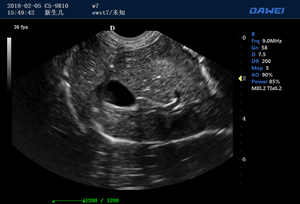

·支持B、C、PW、CW、寬景成像

適用于各種動物的臨床腹部、胸腔,心臟、肌腱、小器官、眼球、生殖系統等的檢查